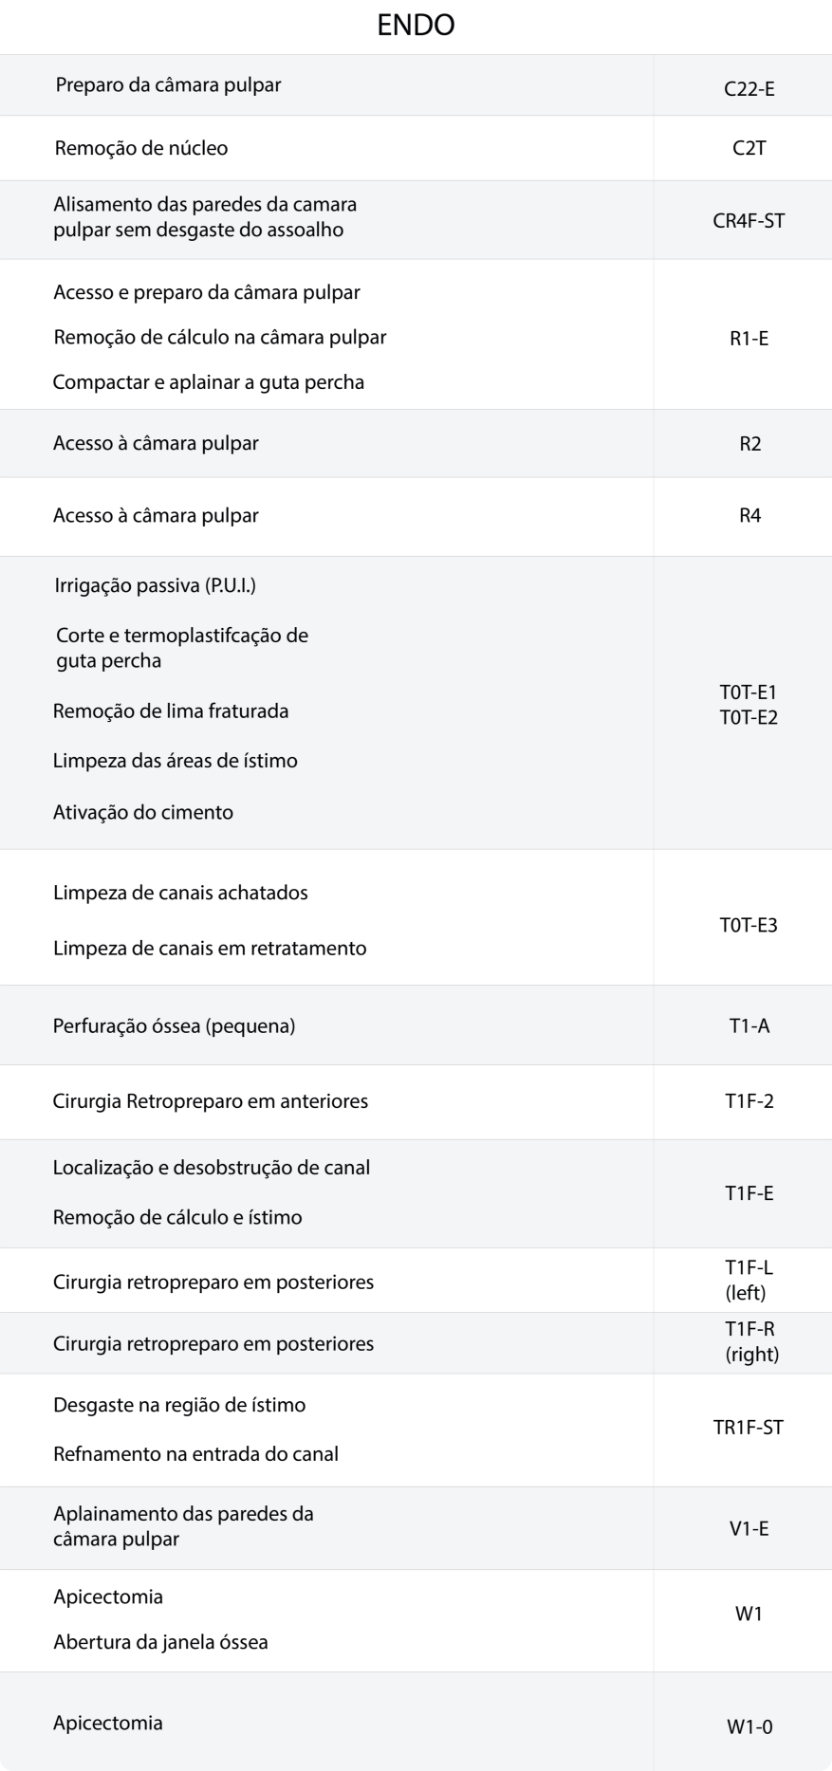

Presente em aproximadamente 60

modelos de pontas do portfólio.